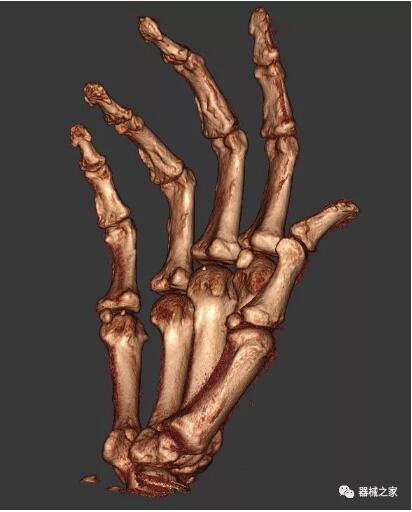

以上介紹的CT均來(lái)自國(guó)外同一家公司,這些CT均配置了可視化軟件,可以進(jìn)行切片、3D重建以及大型CT附帶的所有典型的操作功能。

以下是這些“特立獨(dú)行”的CT所拍出來(lái)的圖像: